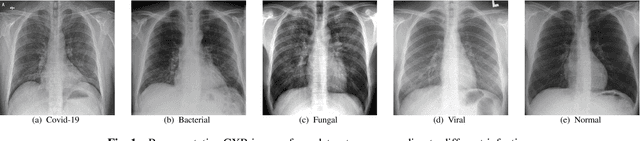

Abstract:The novel corona virus (Covid-19) has introduced significant challenges due to its rapid spreading nature through respiratory transmission. As a result, there is a huge demand for Artificial Intelligence (AI) based quick disease diagnosis methods as an alternative to high demand tests such as Polymerase Chain Reaction (PCR). Chest X-ray (CXR) Image analysis is such cost-effective radiography technique due to resource availability and quick screening. But, a sufficient and systematic data collection that is required by complex deep leaning (DL) models is more difficult and hence there are recent efforts that utilize transfer learning to address this issue. Still these transfer learnt models suffer from lack of generalization and increased bias to the training dataset resulting poor performance for unseen data. Limited correlation of the transferred features from the pre-trained model to a specific medical imaging domain like X-ray and overfitting on fewer data can be reasons for this circumstance. In this work, we propose a novel Graph Convolution Neural Network (GCN) that is capable of identifying bio-markers of Covid-19 pneumonia from CXR images and meta information about patients. The proposed method exploits important relational knowledge between data instances and their features using graph representation and applies convolution to learn the graph data which is not possible with conventional convolution on Euclidean domain. The results of extensive experiments of proposed model on binary (Covid vs normal) and three class (Covid, normal, other pneumonia) classification problems outperform different benchmark transfer learnt models, hence overcoming the aforementioned drawbacks.